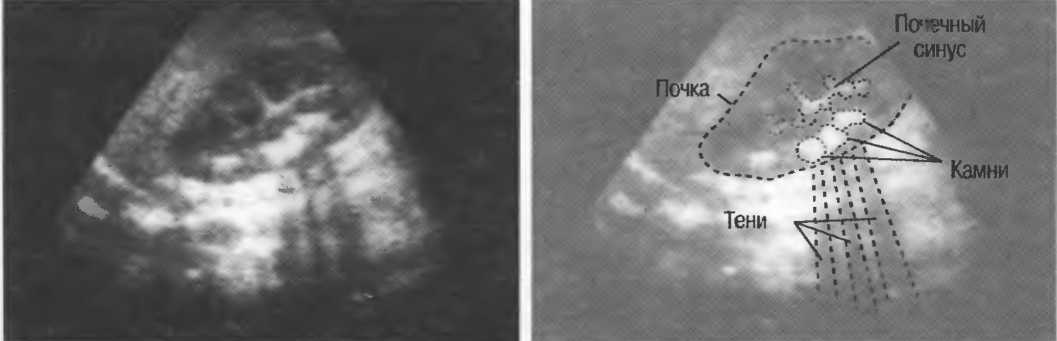

Тени

Кости, камни и кальцинаты дают акустическую тень. Ультразвук не может проходить через кость, если она только не очень тонкая (как, например, кости черепа у новорожденного). При необходимости рассмотреть структуры, расположенные глубже, необходимо использовать различные углы наклона датчика (рис. 17а,б).